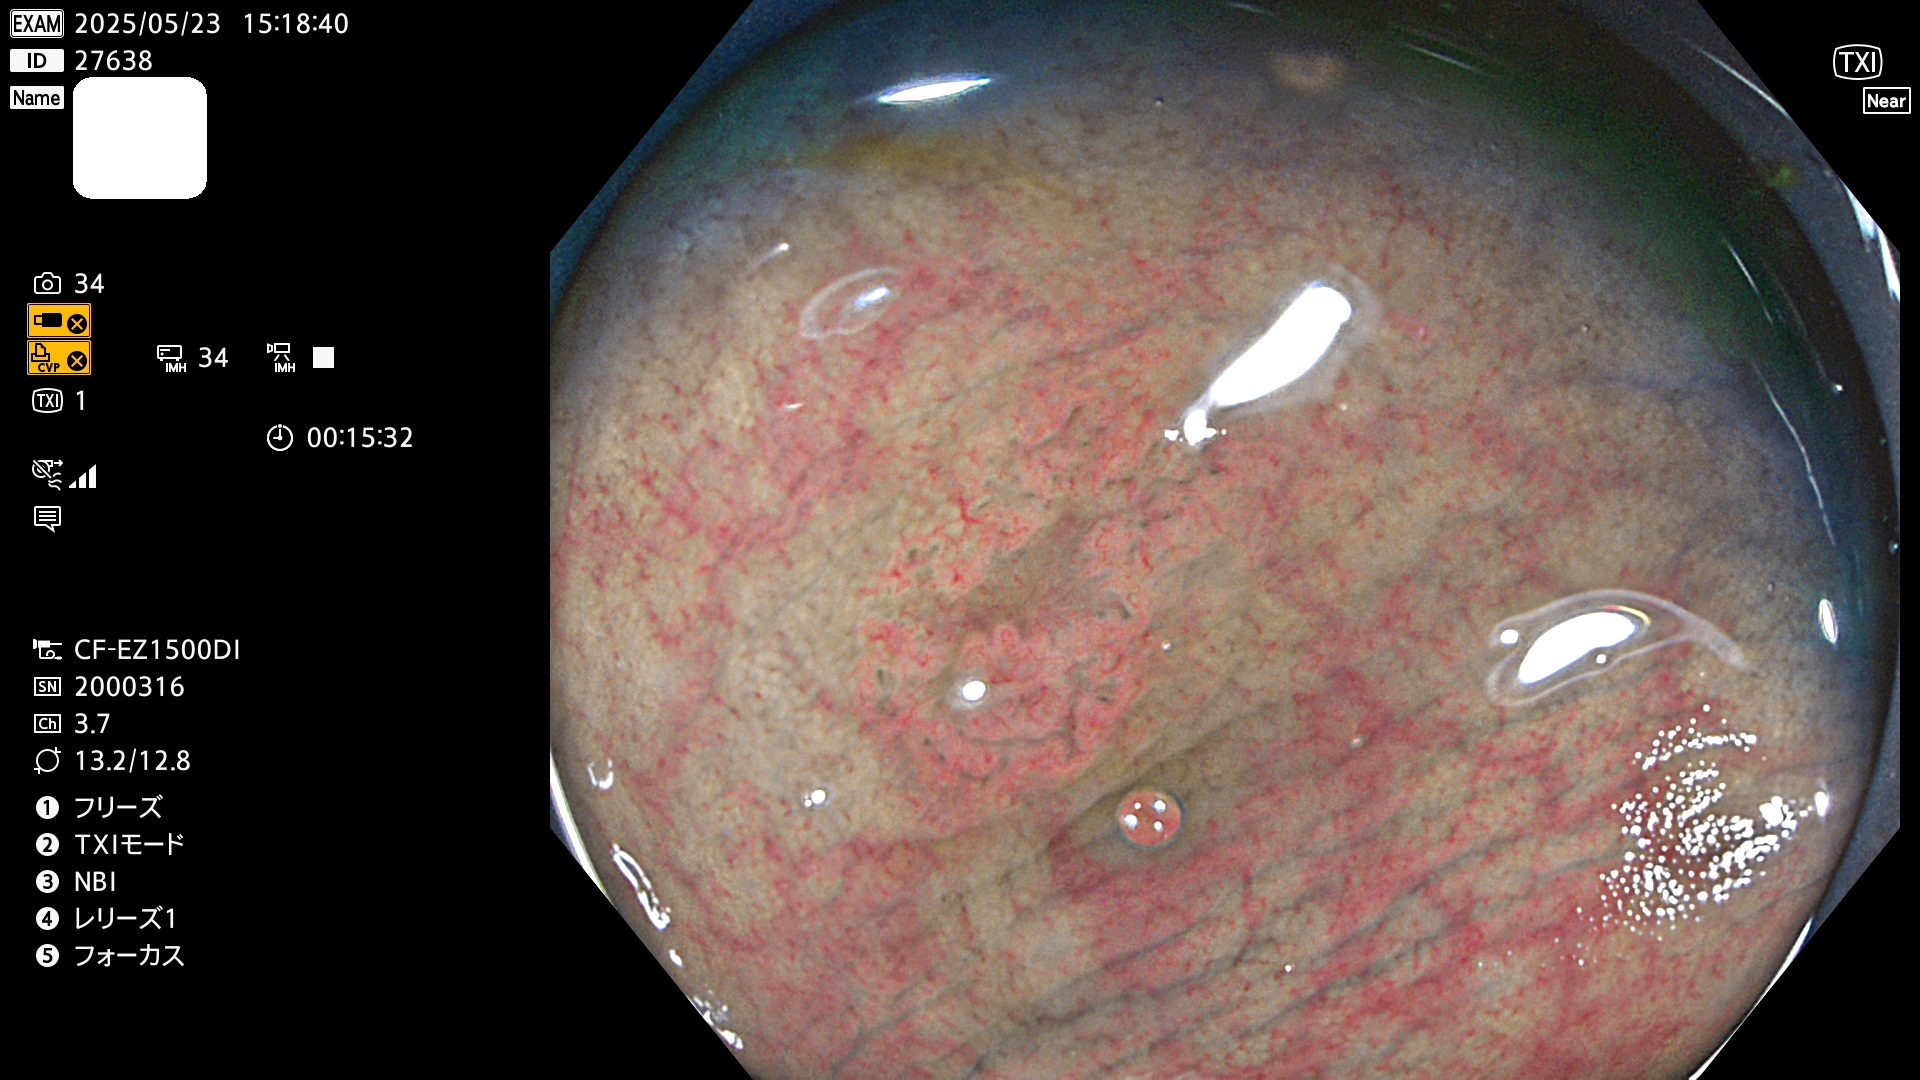

今週のUb、Uc型腺腫

完全に平坦な物をUb、陥凹している物をUcと呼びます。Ubは認識が困難で、Ucはびらん(炎症)と紛らわしいために見落とされやすく、「内視鏡後・大腸癌」の原因になります。

抽出の対象期間 2025年5月22日〜5月25日の4日間(48件の検査)10個 (10/48=21%)